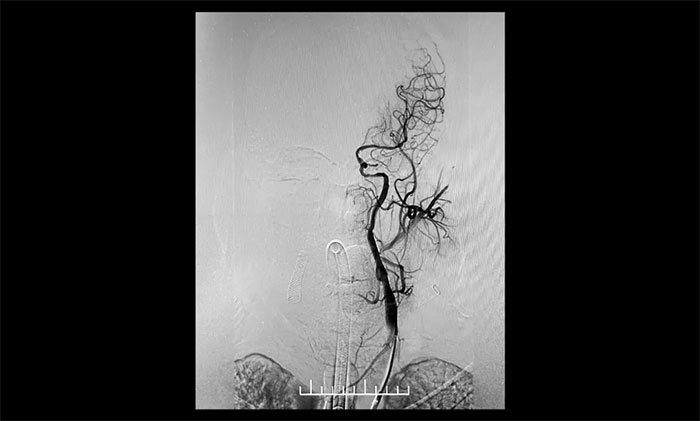

▲ 右颈内动脉起始段重度狭窄

双侧颈内动脉起始段狭窄90%,并且左侧颈动脉属于串联病变。根据患者临床症状及造影结果,席刚明教授、王贵平博士考虑患者双侧大脑半球血流明显灌注不足,属于卒中高危病人,如不开通颈内动脉,反复脑梗死风险极高。但是,如果同时处理两侧颈动脉发生高灌注综合症风险高。